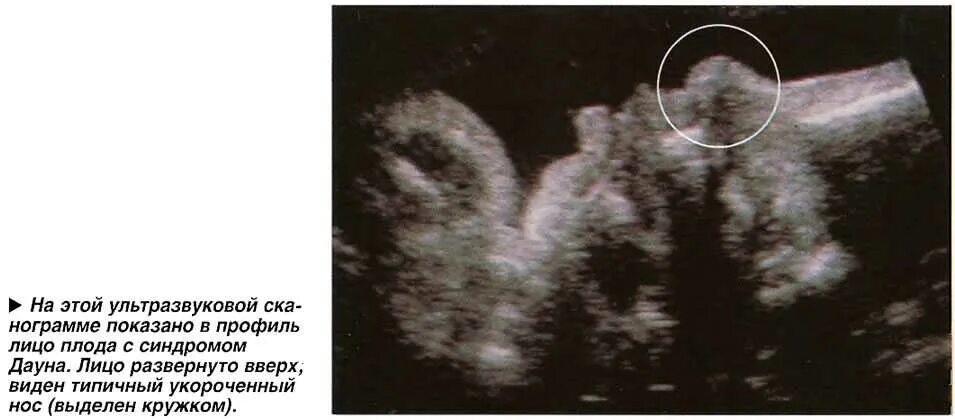

Узи аномалий